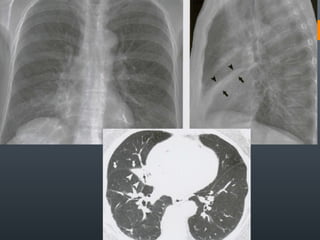

O documento discute vários conceitos radiológicos incluindo consolidação, atelectasia, nódulos, pseudocavidades e padrões intersticiais, fornecendo definições, sinais e diagnósticos diferenciais para cada tópico. Ele também discute a redução da atenuação pulmonar e fornece um link para mais informações.